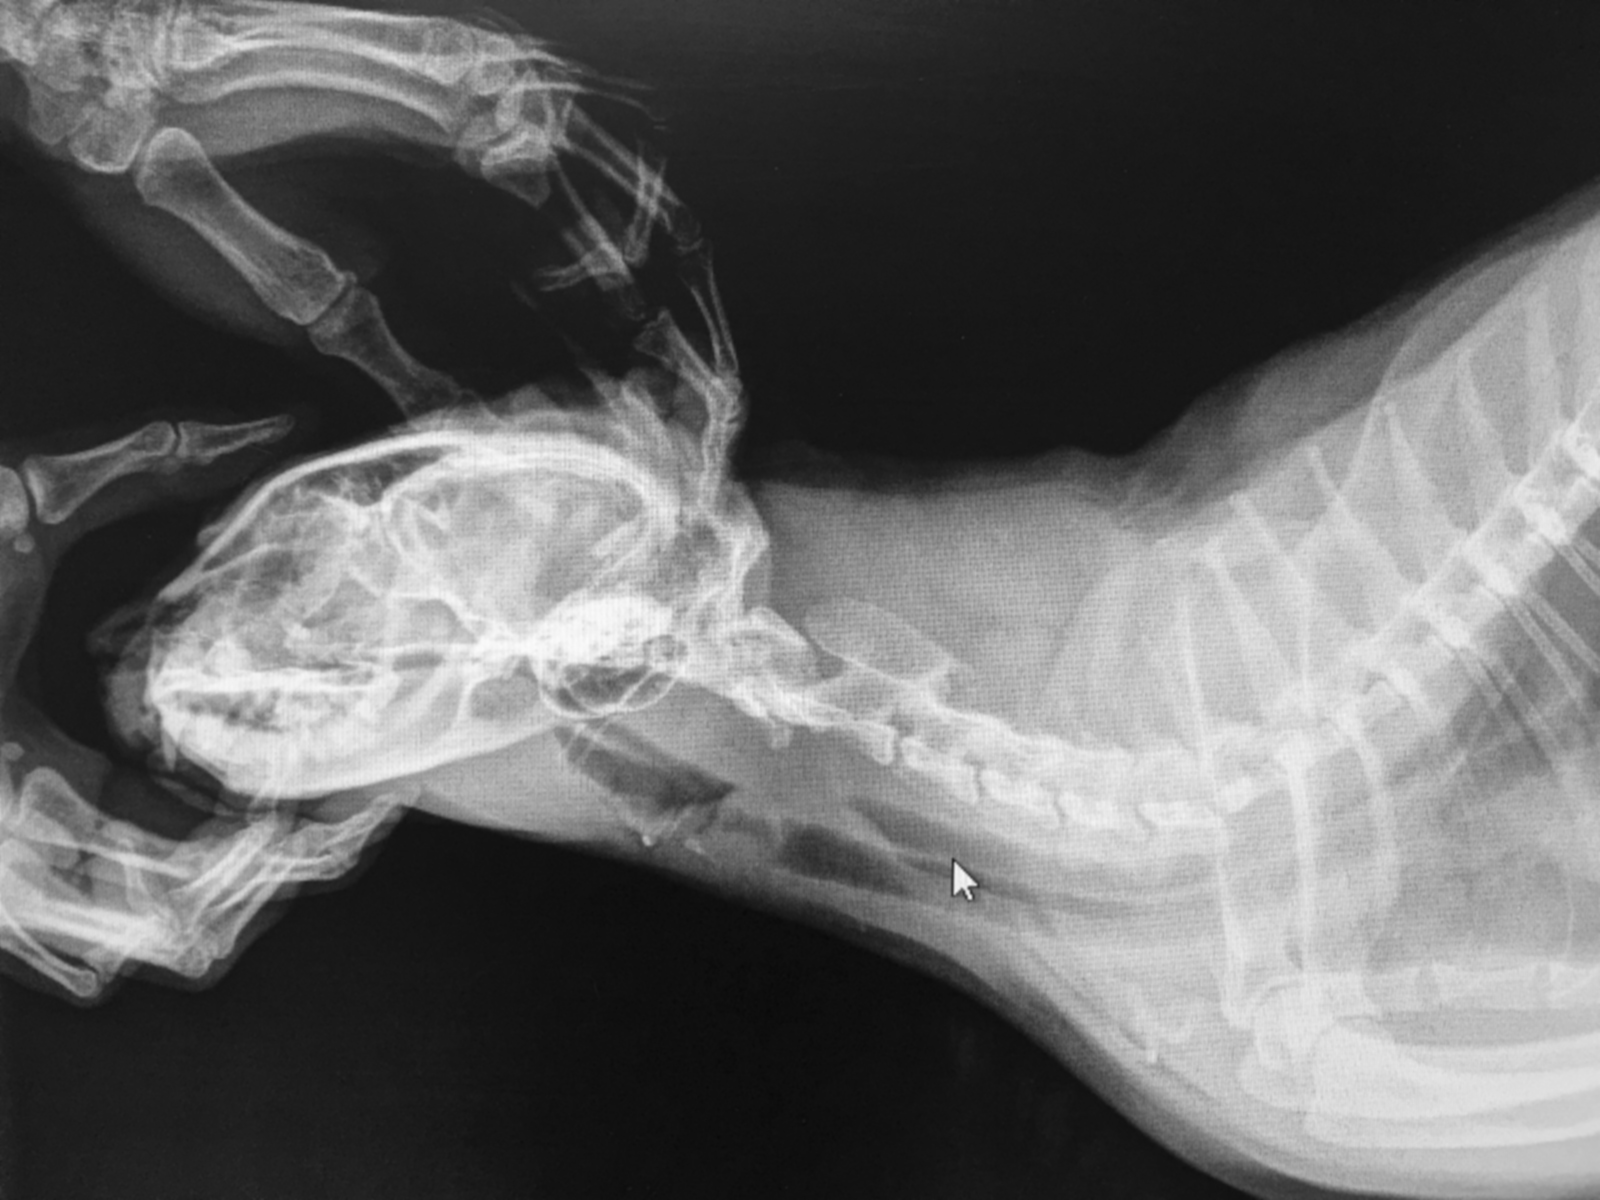

The video describes how to use radiation shielding if you must manually restrain an animal during a radiography examination. Federal guidelines in the United States and Canada recommend that individuals should avoid regular manual restraint of animals for radiographs, but if you must do so, it’s important to follow these guidelines that are designed to protect your health.

7 minute video on radiation safety in small animal radiography, courtesy of the University of Saskatchewan